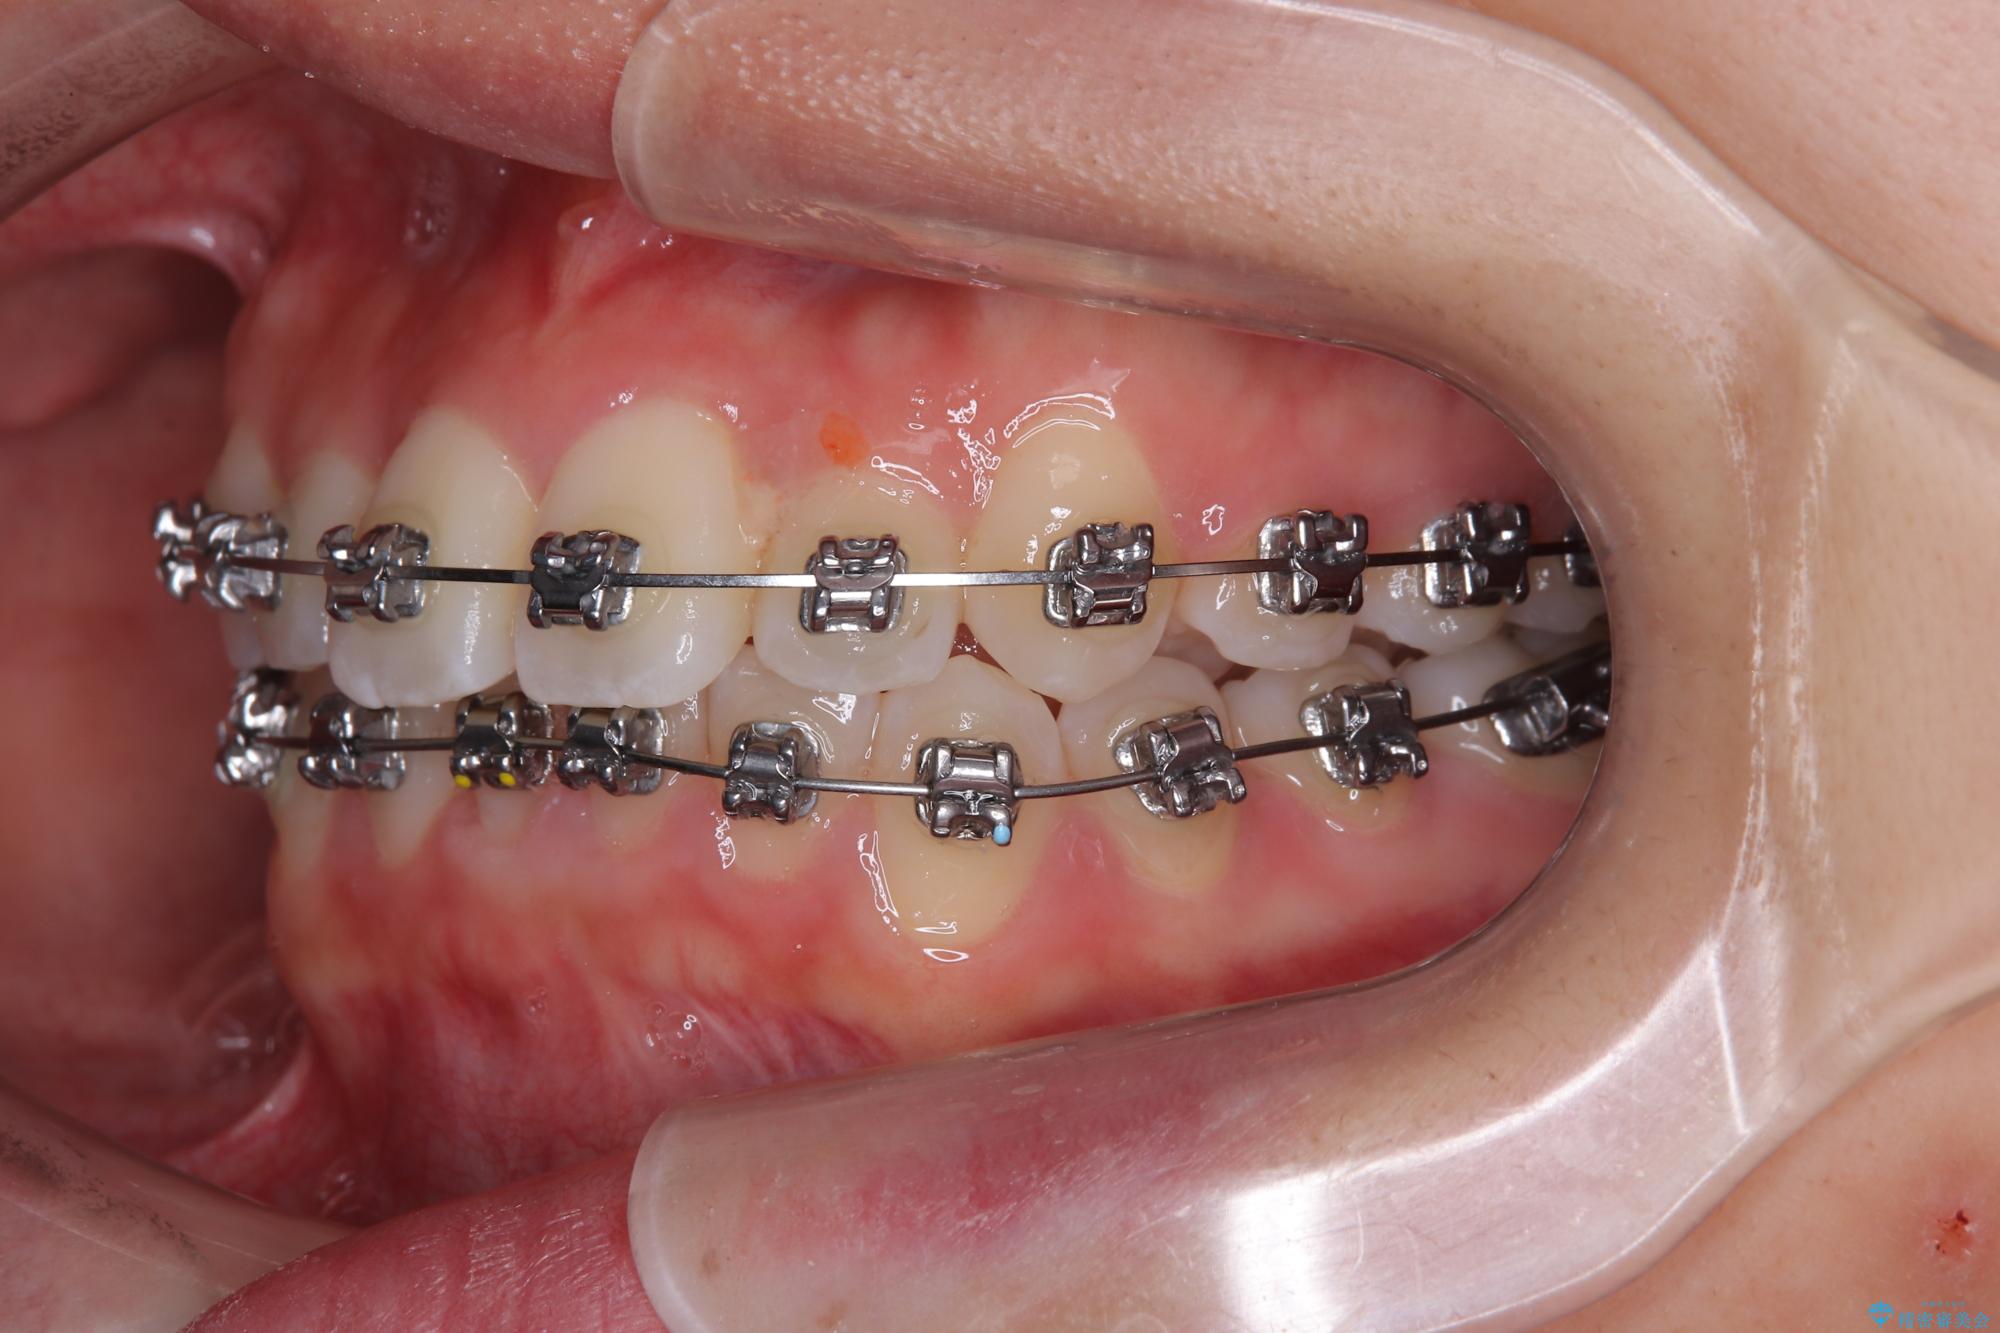

装置の外見を気にしていましたが、短期間で治療を終えることができるだろうと伝えると、安価であるメタルブラケットを選択されました。

想定通り、1年強で綺麗に仕上げることができました。